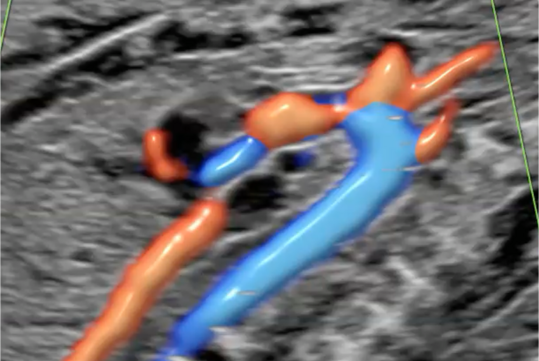

Ultraschalluntersuchung der mütterlichen und kindlichen Durchblutung (Farb-Dopplersonografie)

Die Durchblutung der Nabelschnur, der kindlichen Gefäße und des Mutterkuchens wird mittels einer speziellen Ultraschalltechnik durchgeführt. Mit der sogenannten (Farb-)Dopplersonografie können wir in der Pränataldiagnostik und Schwangerenambulanz die Versorgungslage überprüfen.

Auffällige Blutflussmuster können auf eine Mangelversorgung des Ungeborenen oder Auffälligkeiten im Kreislauf der Mutter hinweisen. Zu nennen wäre hier das erhöhte Risiko für einen schwangerschaftsbedingten Bluthochdruck. Mittels der Untersuchung können solche Probleme rechtzeitig erkannt und die Patientin entsprechend am UKS überwacht werden.

Nabelschnurarterie

Gehirndurchblutung (A. cerebri media)